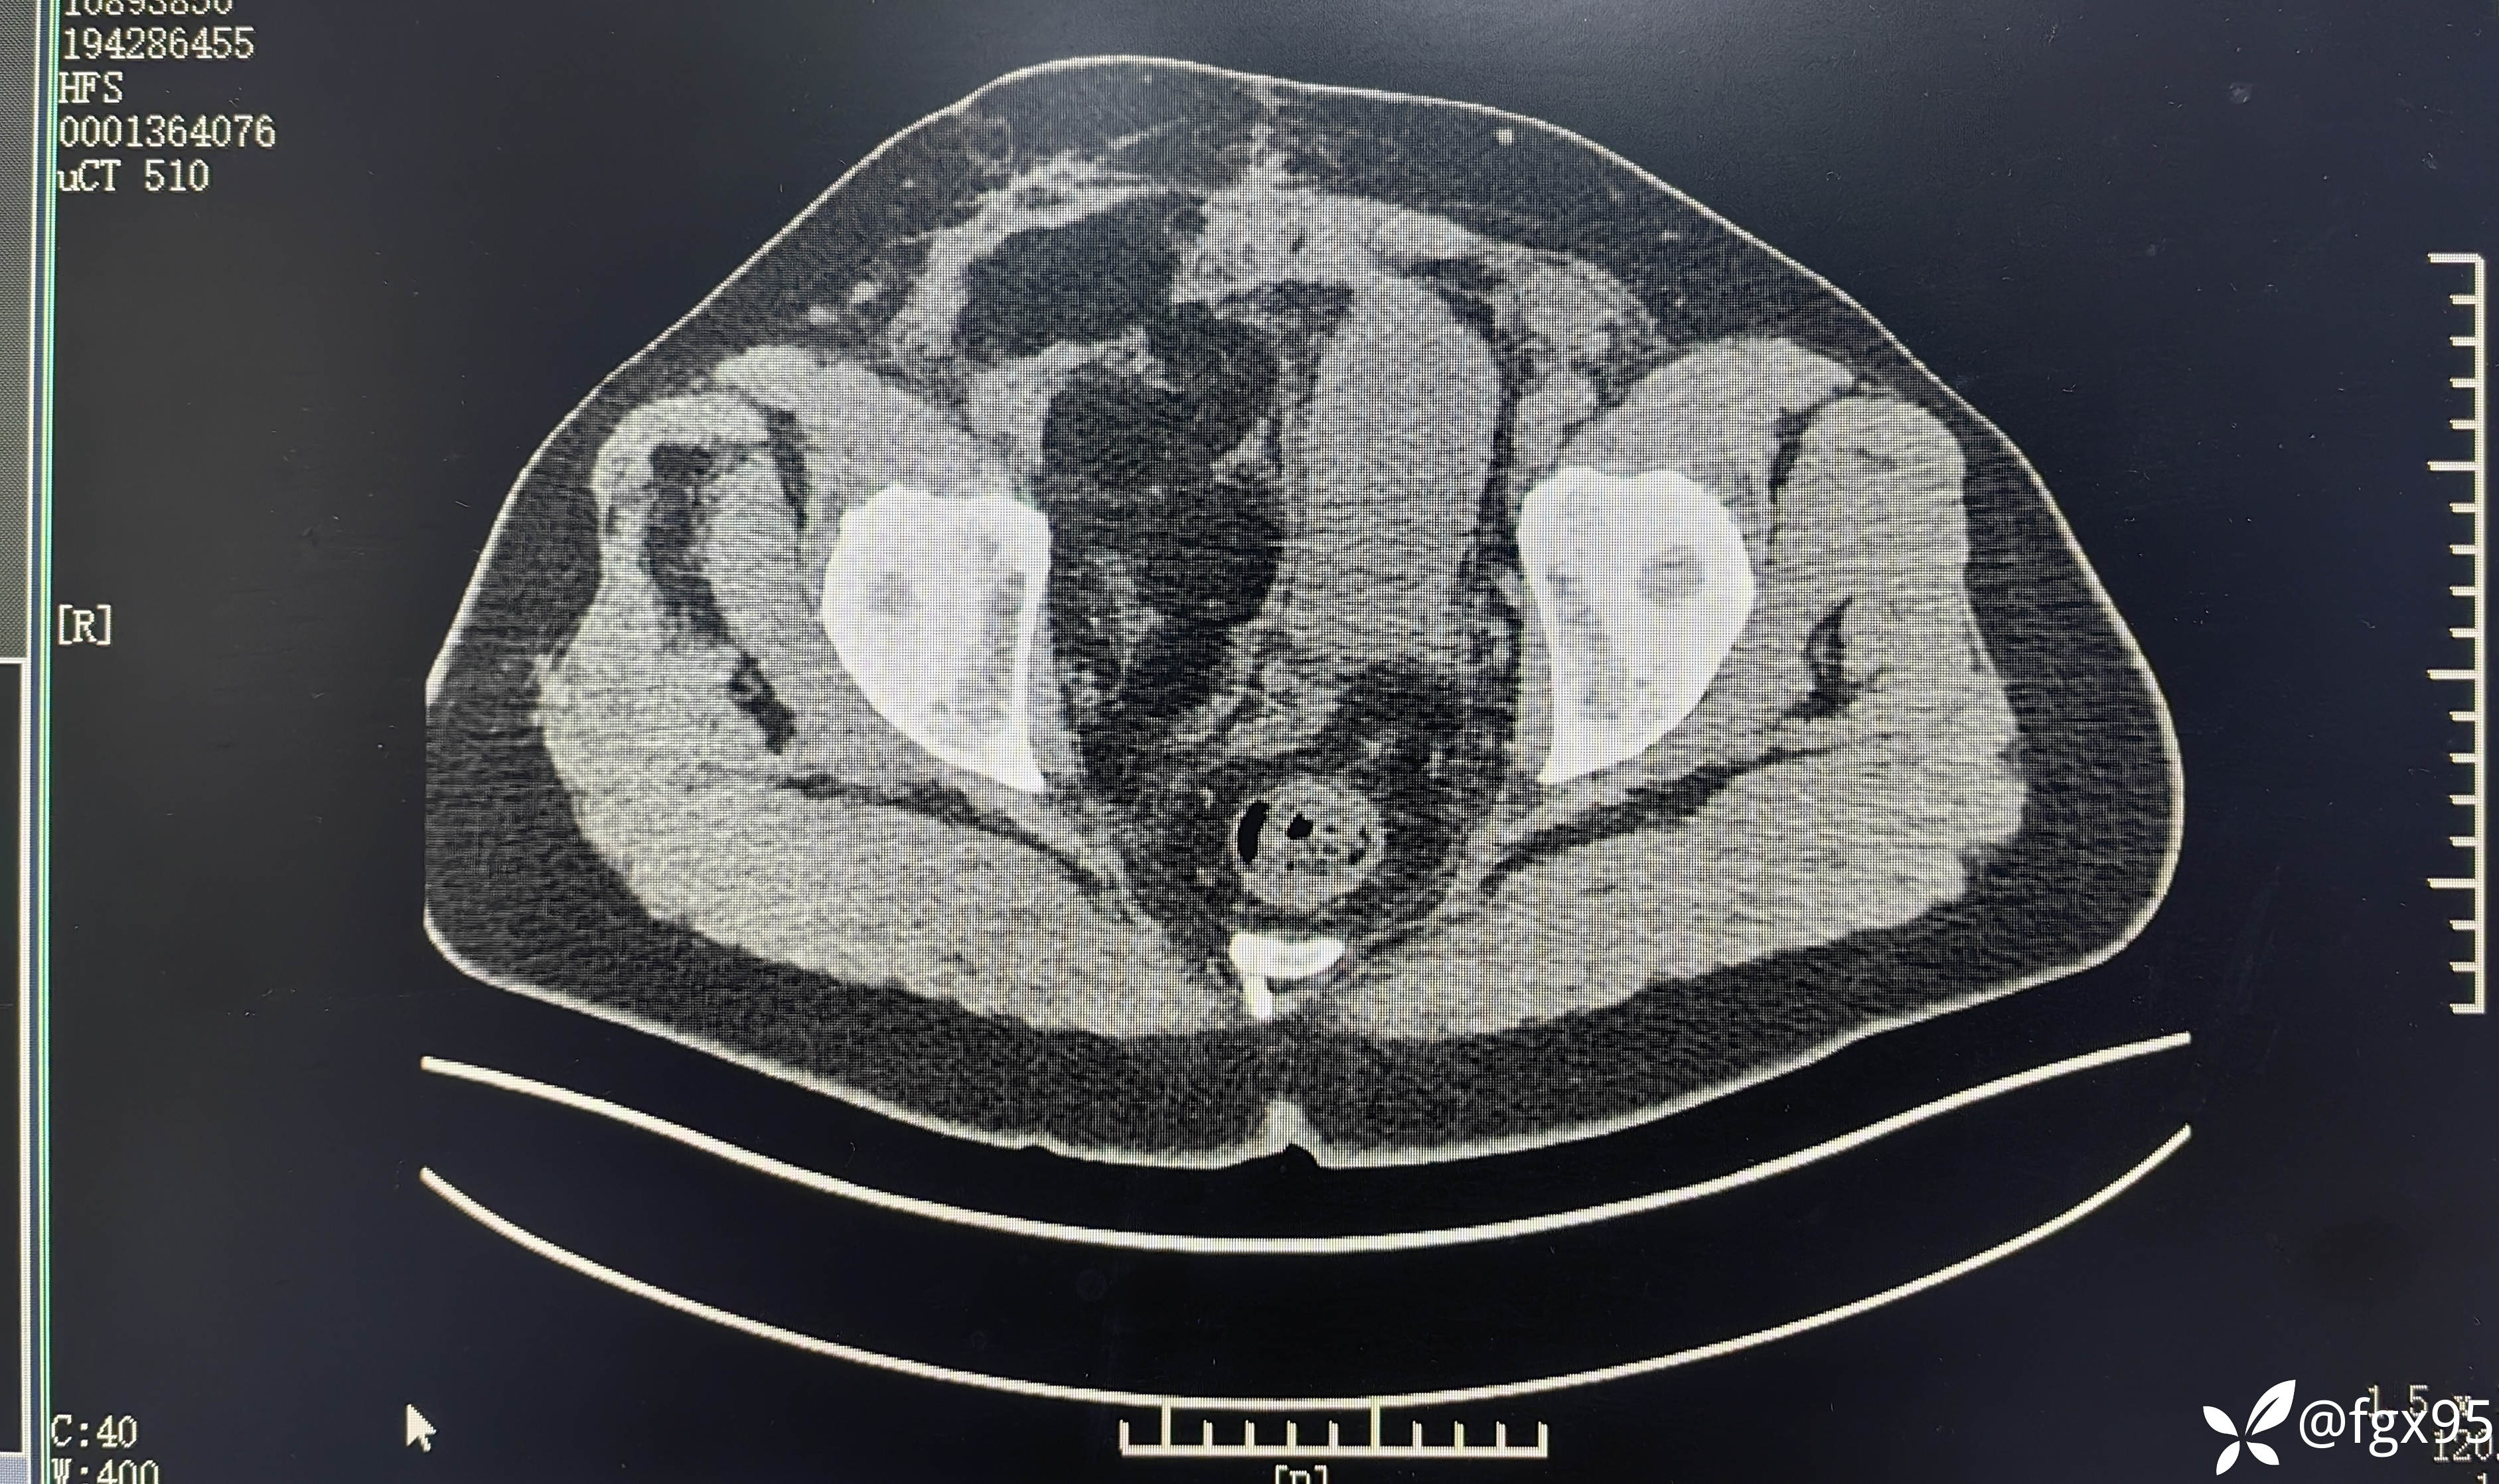

2024年复查腹盆腔+双下肢增强 CT 示:脂肪肉瘤术后,右侧盆腔至腹股沟区复发转移灶;右髋肌间隙复发灶。

第三次手术前盆腔CT